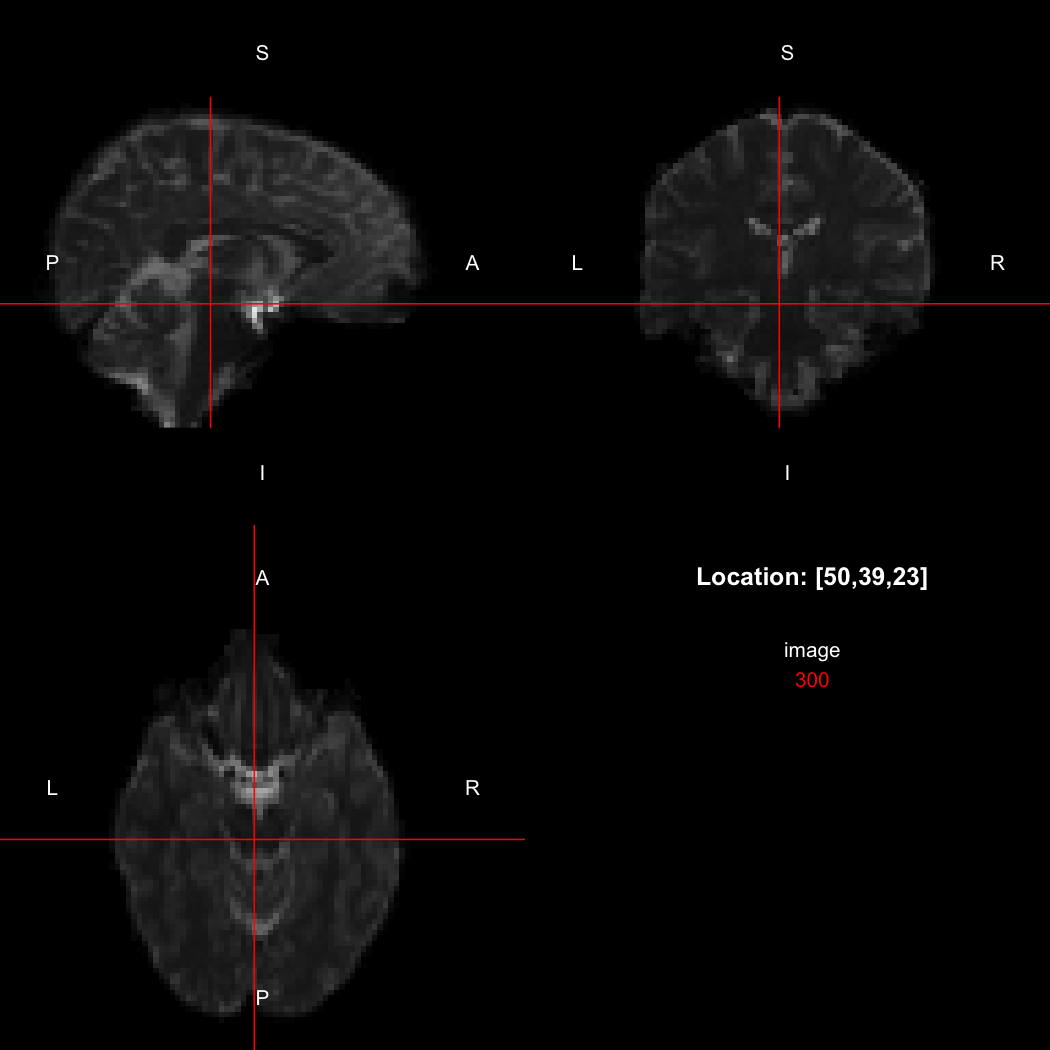

The package contains a basic image viewer, which can be used interactively or noninteractively to examine 2D or 3D images.

view(image)

plot of chunk unnamed-chunk-5

By default, the viewer shows labels indicating image orientation, crosshairs pinpointing the currently selected location, the numerical indices of the current location, and the value of the image at that location. Options allow each of these to be turned off, for the content of the bottom-right panel to be customised entirely, for the colour scale to be changed, and for additional images to be layered on top of the base image. See ?view for details.

In this case, the image is flipped along the x-axis relative to the canonical axes, so the positive x-direction points towards the left rather than the right. This is compactly represented by the output of the orientation function, which indicates the approximate real-world directions of the positive axes in each dimension.

orientation(image)

## [1] "LAS"

So, here, “LAS” means that the positive x-axis points left, the positive y-axis anterior and the positive z-axis superior. This is the so-called “radiological” orientation convention, and can be requested when viewing images for those who are used to it:

view(image, radiological=TRUE)

plot of chunk unnamed-chunk-12

Notice the left (L) and right (R) labels, relative to the view shown above. Setting the radiologicalView option to TRUE will make this the default for all future views.